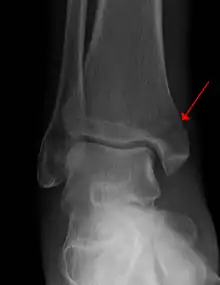

Example of an intraarticular fracture of the medial malleolus extending in the talocrural ankle joint

An intraarticular fracture is a bone fracture in which the break crosses into the surface of a joint. This always results in damage to the cartilage.[1] Compared to extraarticular fractures, intraarticular have a higher risk for developing long-term complications, such as posttraumatic osteoarthritis.[2]